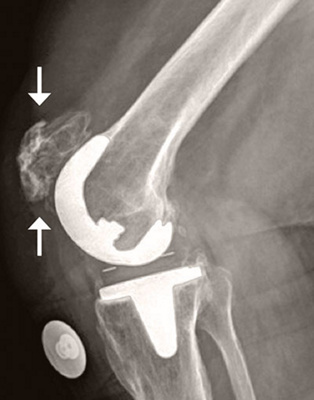

Abb. 2

In der Darstellung des Knochenumbaus lässt sich die Reizung auf die Kniescheibe und eine Lockerung des Prothesenanteils am Unterschenkelknochen rechts darstellen.

Als nächster Schritt erfolgte eine nuklearmedizinische Untersuchung in der Radiologie der Klinik St. Anna, ein sogenanntes SPECT-CT. Dabei wird der Knochenumbau mit Hilfe eines Medikaments sichtbar gemacht, das vorgängig über eine Infusion verabreicht wird (Abb. 2). Die gesamte Untersuchung kann mit Pausen bis zu vier Stunden dauern. Durch diese hochspezialisierte Technik können auch Probleme der Knieprothese erkannt werden, die im Röntgen unsichtbar sind. Die Untersuchung von Andrea Ohnsorg ergab, dass die Kniescheibe gereizt und ein Teil der Prothese gelockert war.